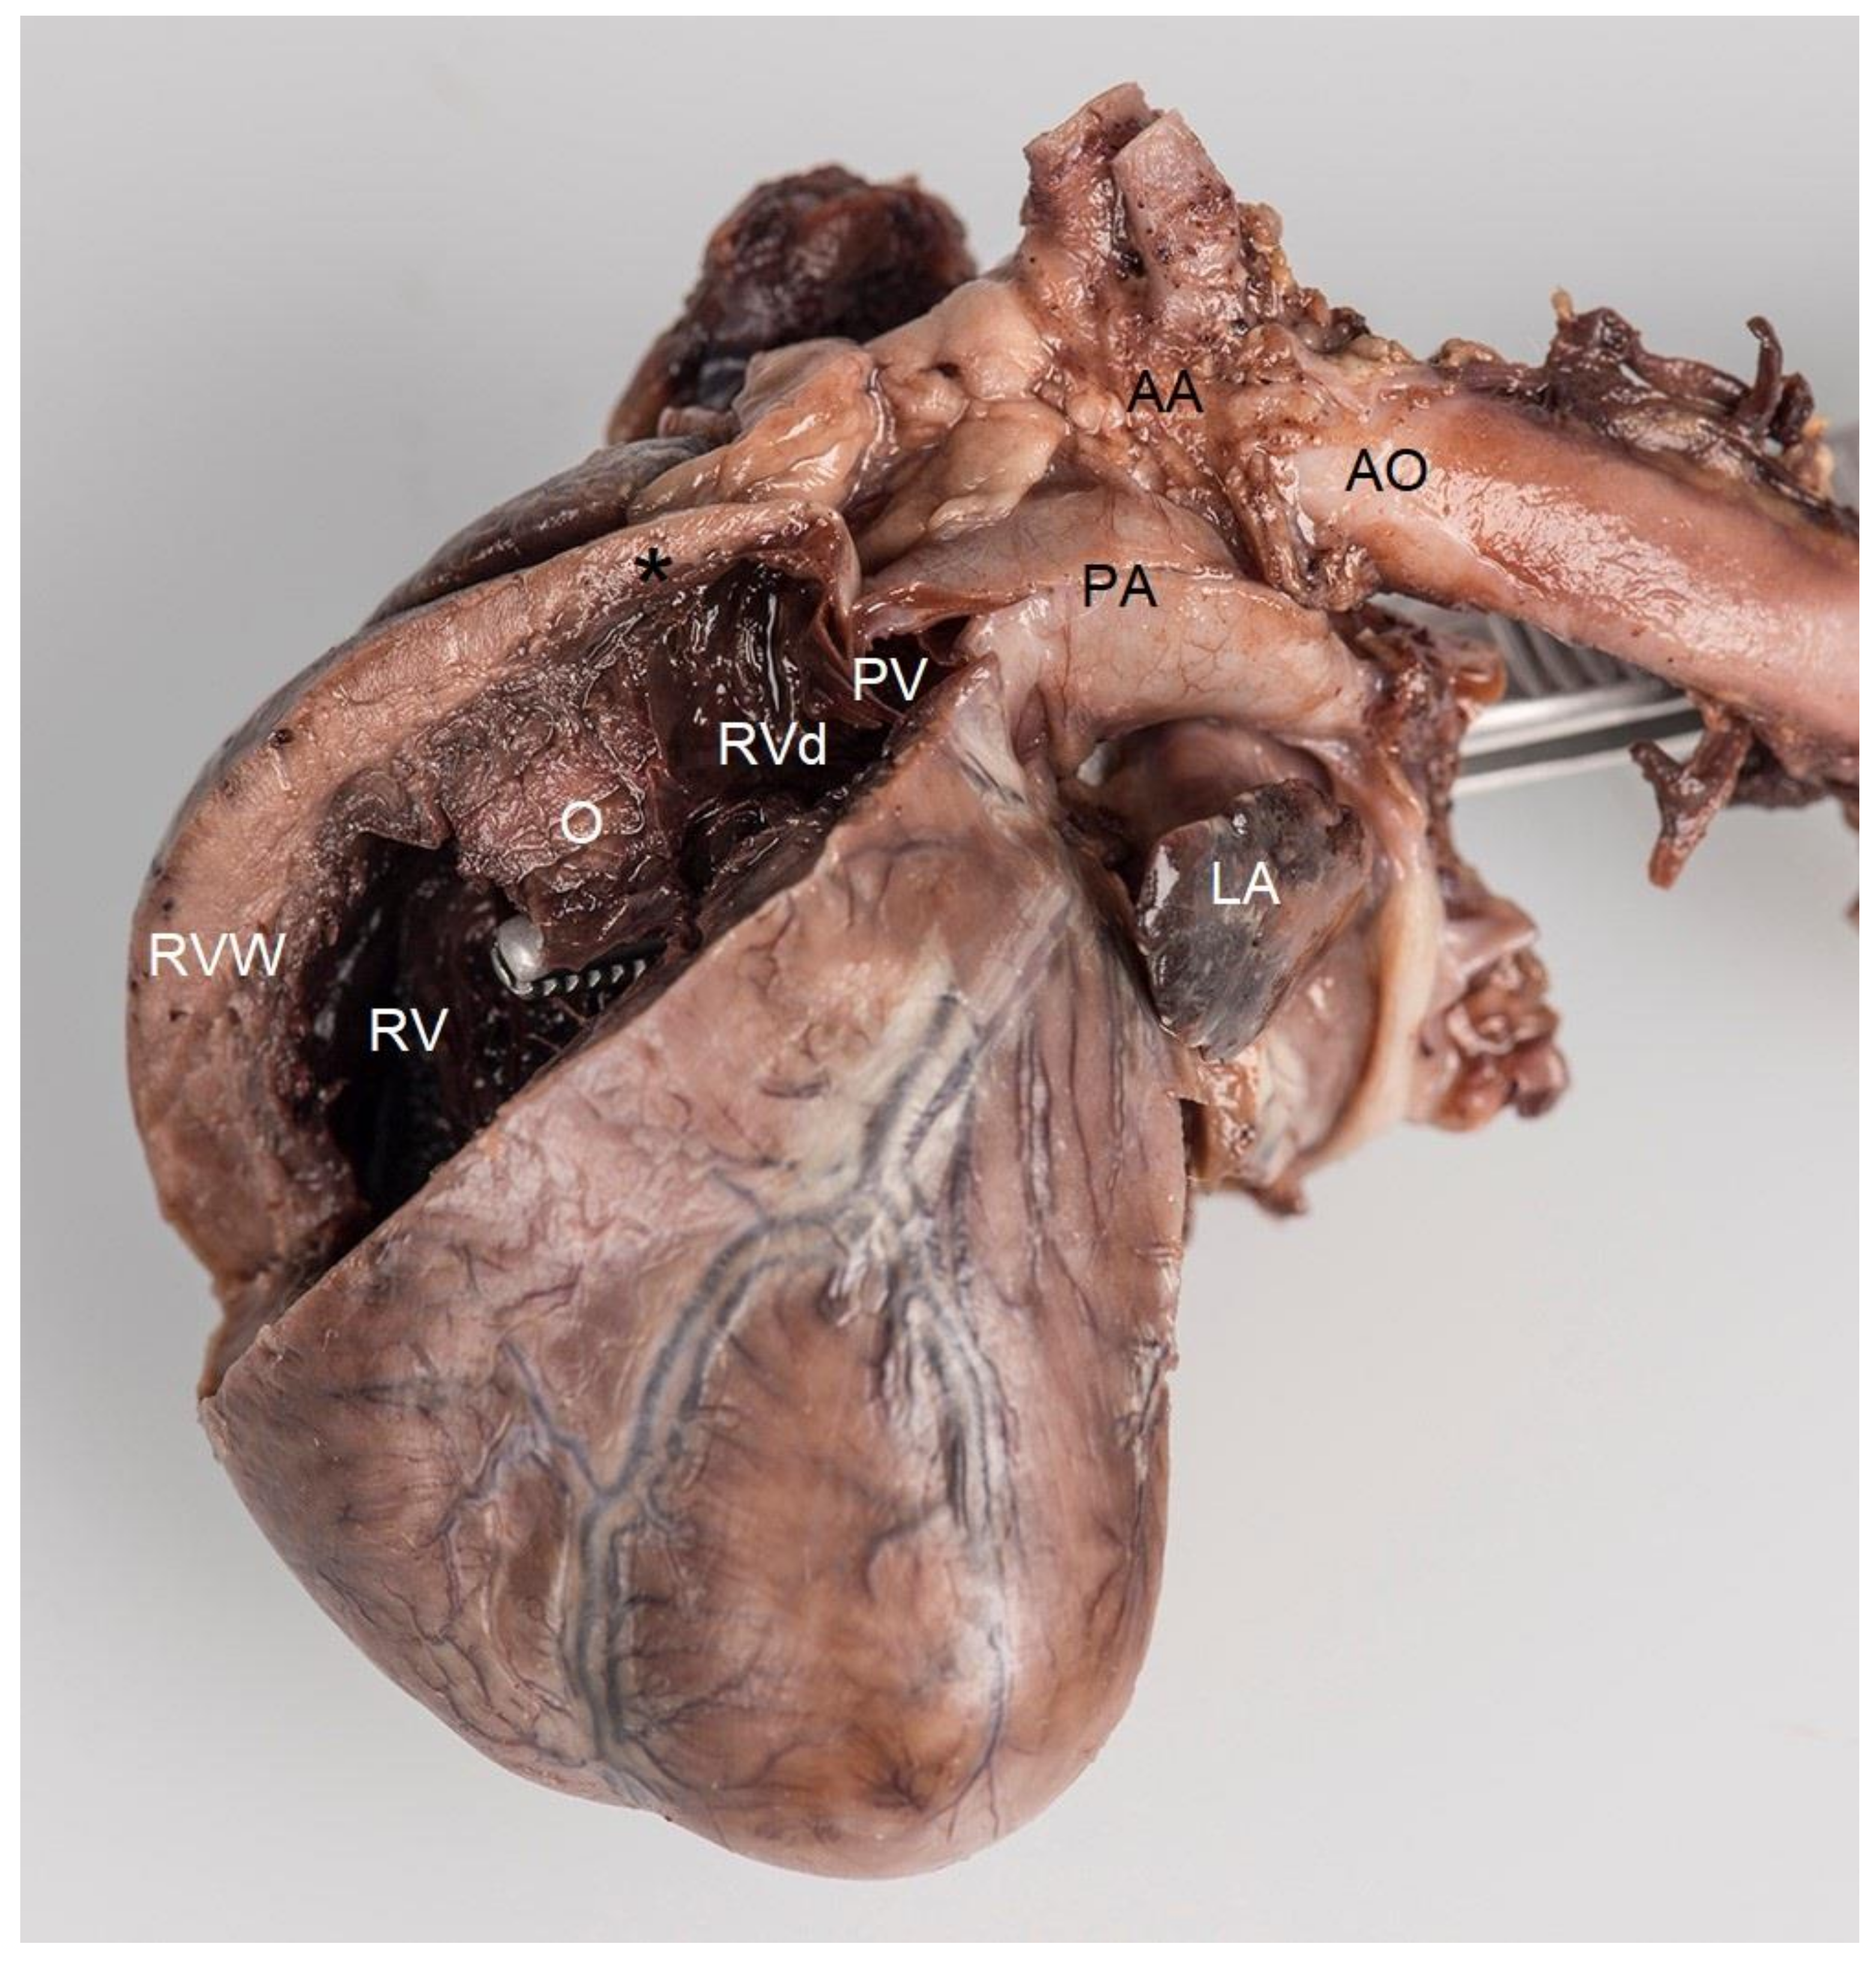

Because of a poor long-term prognosis, the owner elected for euthanasia, which was performed by the referring veterinarian. The heart was removed from the cadaver, placed in a 10% neutral buffered formalin solution, and returned to the authors’ institution for post-mortem examination. A gross macroscopic investigation of the specimen confirmed the echocardiographic findings. The heart measured 3.0 × 1.5 × 1.0 cm. The right atrial appendage showed a mild dilation (2.0 × 1.0 × 1.0 cm), while the left atrial appendage was very small (1.5 × 1.0 × 0.2 cm). The interventricular septum and both the left and right ventricular free walls measured 5 mm, indicating a moderate right ventricular hypertrophy. A perimembranous ventricular septal defect was noted. In the right ventricle, an atypical muscular bundle of 5 mm in diameter was identified (Figure 6).

Figure 6. Post-mortem formaldehyde-fixed heart viewed from the left side. The right ventricular free wall was removed to disclose its lumen. Localized muscular hypertrophy in the right ventricular chamber (O) results in a concentric hypertrophy of the right ventricle proximal to the obstruction (RV) as evidenced by a thick right ventricular free wall (RVW), compared to the right ventricular chamber distal to the obstruction (RVd), which has a normal wall thickness (black *). The forceps were introduced from the left ventricle through the ventricular septal defect with its tip in the right ventricle. Note that the tip of the forceps, i.e., the opening of the ventricular septal defect, is very close and proximal to the localized muscular hypertrophy (O). AA—aortic arch, AO—descending aorta, PA—pulmonary artery trunk, PV—pulmonic valve, LA—left auricle.